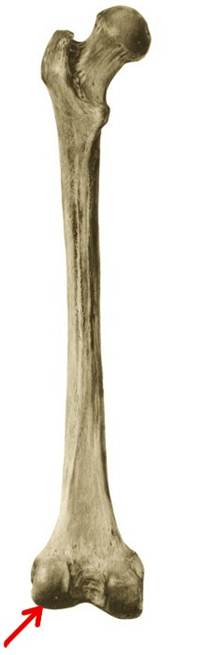

S: Стрелка указывает на linea supracondylaris medialis

S: Стрелка указывает на linea supracondylaris lateralis

S: Стрелка указывает на linea supracondylaris medialis

S: Стрелка указывает на condylus medialis

S: Стрелка указывает на linea aspera

S: Стрелка указывает на facies poplitea (латинский язык).